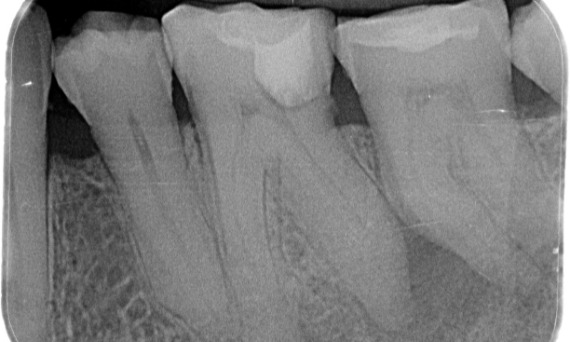

Before: Periapical radiolucency associated primarily with the distal root and loss of lamina dura on the mesial root.

After: TruNatomy was chosen in this case to allow a caries leveraged approach and a focus on pericervical dentin preservation especially on the mesial aspect where the tooth had a more minimal restoration.